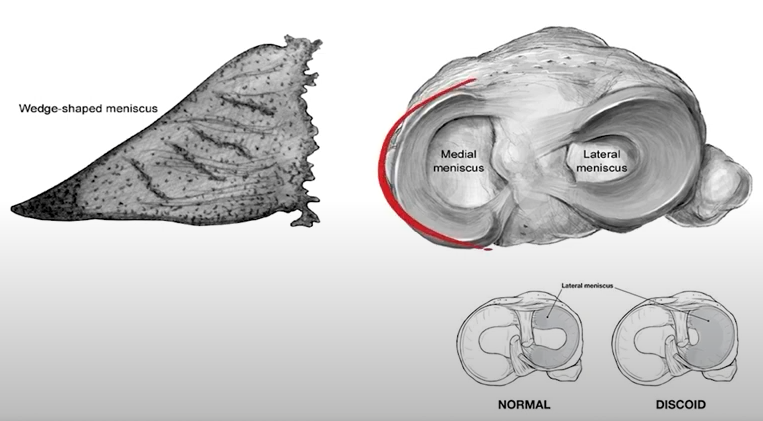

이러한 불안정성을 위해 구슬과 같은 대퇴부위를 잡아주는 해부학적 구조물이 바로 "반월연골판(Meniscus)" 입니다.

탁자위에 고무타이어를 둘러서 구슬이 안빠져나오게 한다고 생각하면 쉽게 이해할 수 있습니다.